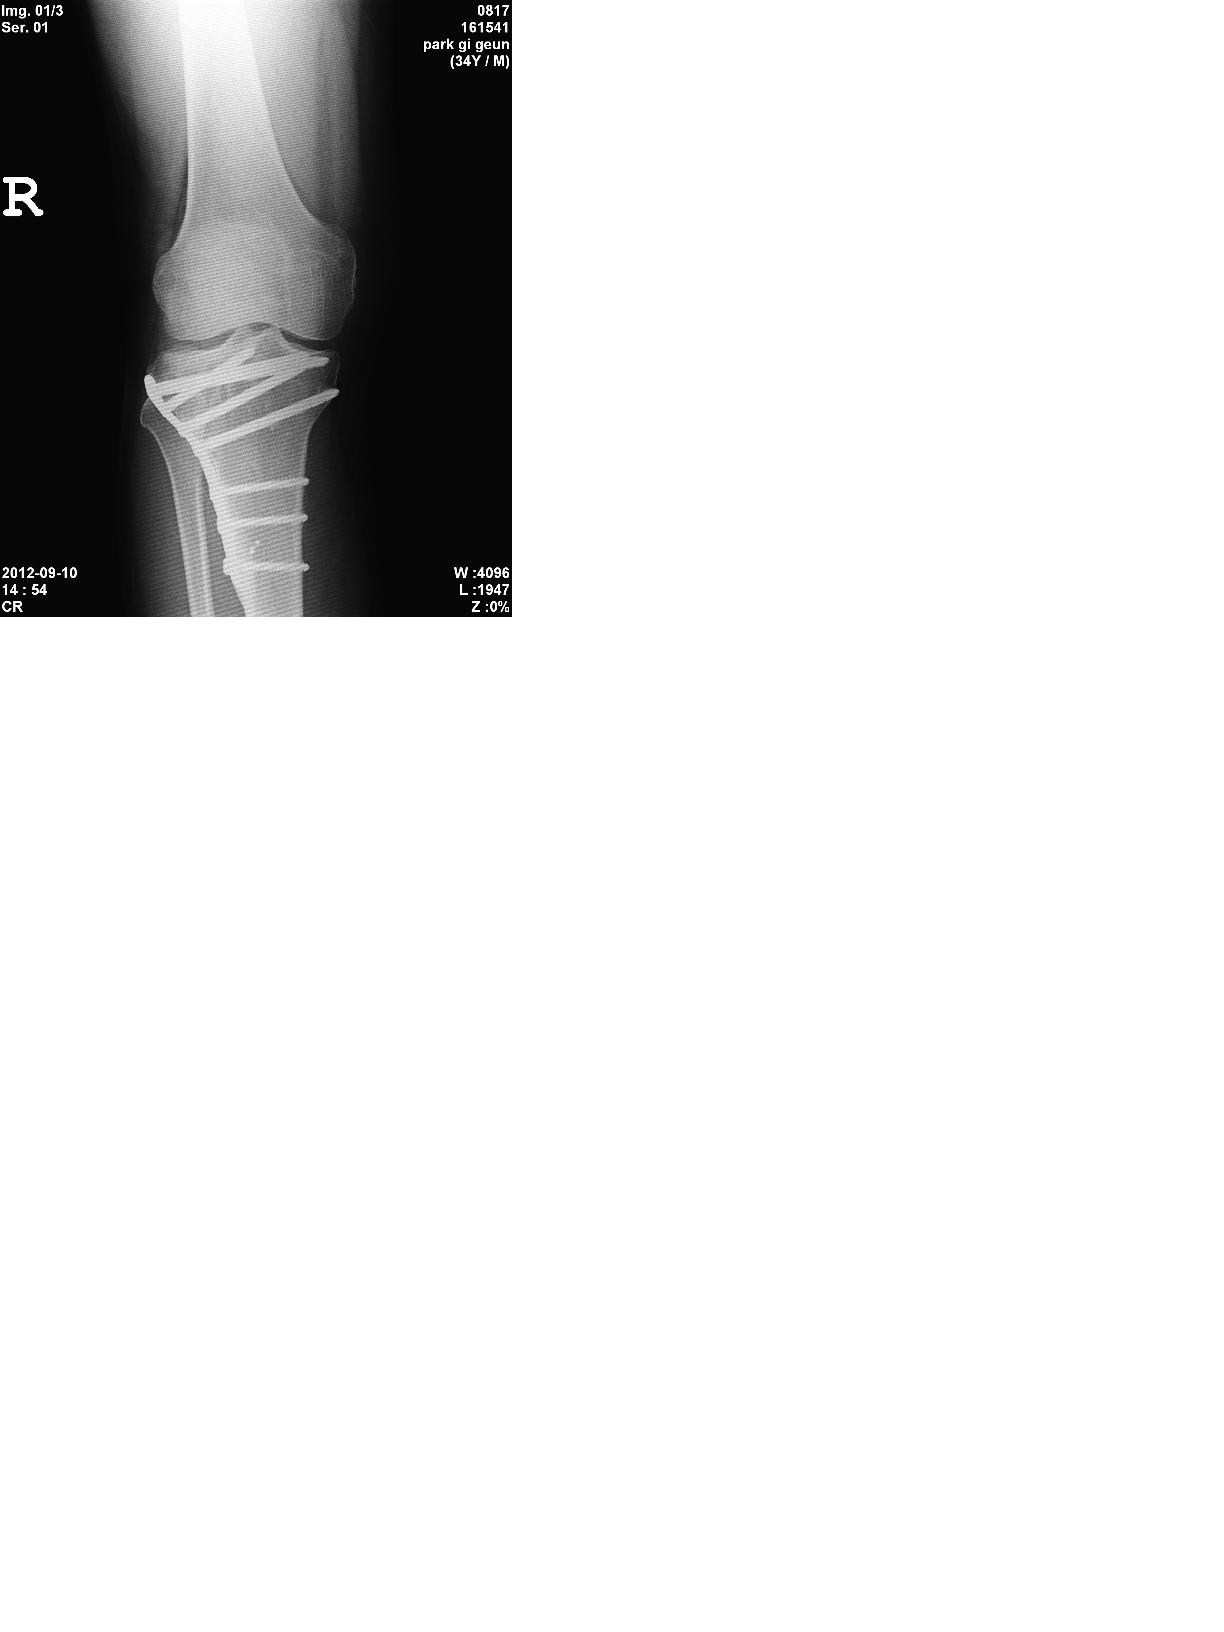

2005년 사고로 연골 떠받드는 부위에 금이가서 핀 고정술을 하였습니다

약간의 관절 강직으로 보행은 무리가 없으나 달리기와 점프 그리고 다 접히지 않는 관절 강직이 좀 있어요

장애 나올까요? ㅎㅎ  수술한 대학병원 교수님은 자존심때문인지 운동 좀더 합시다 이러는데 ㅡㅡ 5개월 넘개 재활 했는데 다 안구부려집니다 ㅠㅠ

전문가들의 답변을 기다립니다 ㅎ'제목 없음3.JPG 제목 없음1.JPG 제목 없음2.JPG

X-ray